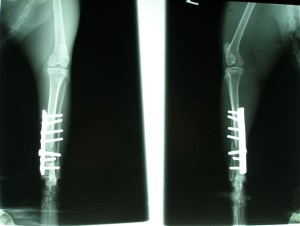

Po operaci obou kostí

kontrolní rentgen měsíc po operaci: 467,-Kč

Teď nás čeká další rentgen. Pokud bude srůst kostí dostatečný, bude Murri muset přestát ještě operaci, kde mu budou vytaženy šrouby. Předpokládané další náklady tedy budou spojené s dalším rentgenem a operací. Cenu budu zítra opět konzultovat / jdeme na vyšetření a zásah s kocourkem, který má problémy v tlamičce/. Pak budeme nožku v průběhu dalších měsíců pomalu zatěžovat tzn, že Murri bude mít krátké, kontrolované procházky a budeme cvičit. Zatím je stále ve velké kleci, která mu dovoluje dost pohybu a bezpečné zatížení nohy. Na nožku zatím výrazně kulhá, nerad ji zatěžuje, myslím, že mnohé je důsledkem ochablé svaloviny. Podstatný bude rentgen.

4. března večer půjde Murri na další kontrolní rentgen. Pak podáme zprávy, jak to vypadá, co nás čeká a kolik to bude stát :-(